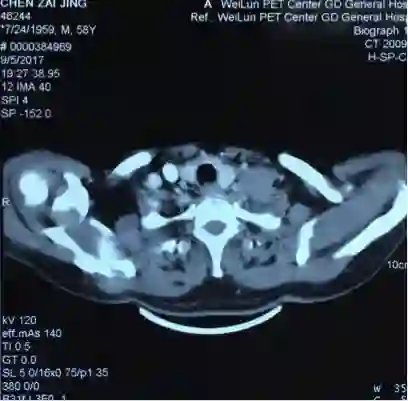

5. 2017-9-5广东省人民医院PET提示:右肺下叶肿物2.8*2.7cm,SUV 22.3,双侧颈部、双侧气管旁、隆突下、食管旁、右侧肺门淋巴结肿大,代谢升高,考虑为转移灶,右侧肾上腺转移灶,具体结果见下图:

7.目前诊断:右下肺肿瘤cT1cN3M1c IVB期(颈部淋巴结、肾上腺)

2.  根据PET/CT目前诊断为右下肺肿瘤cT1cN3M1c IVB期(颈部淋巴结、肾上腺)